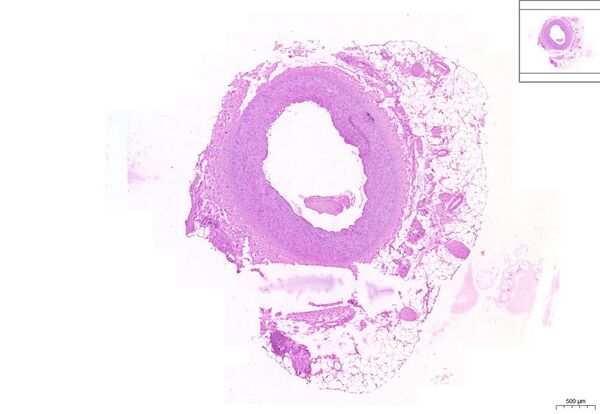

Muscular artery HE 1,9x

Muscular artery HE

- 1. TI - tunica intima

- a)E – endothelium

- b) MEI – membrana elastica interna

- 2.TM - tunica media

- a) JSB - muscle cell nucleus

- b) EV - elastic fibres

- 3. MEE- membrana elastica externa

- 4. TA - tunica adventicia

- 5. TT - adipose tissue

- 6. K – blood

- 7. C - blood vessels (vasa vasorum)

- a) A – artery

- b) V - vein

- 8. L - lumen

- 9. N – nerves